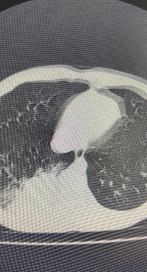

通常医生会采用肺部CT,来寻找“病灶”的大致方位。但若犄角旮里出现“阴影”或不明原因肺部感染,导致无法辨别“真身”时,就得派出“侦察兵”——支气管镜了。通俗的说,支气管镜就是把镜子伸到气管或支气管里,观察气管和支气管的病变,并根据病变进行相应的检查和治疗。

一位重症肺炎儿童,在经验性针对支原体感染阿奇霉素抗感染治疗无效,经气管镜下处理,吸引出痰栓,灌洗液NGS检查提示明确为耐阿奇霉素支原体肺炎,调整治疗后迅速病愈出院。